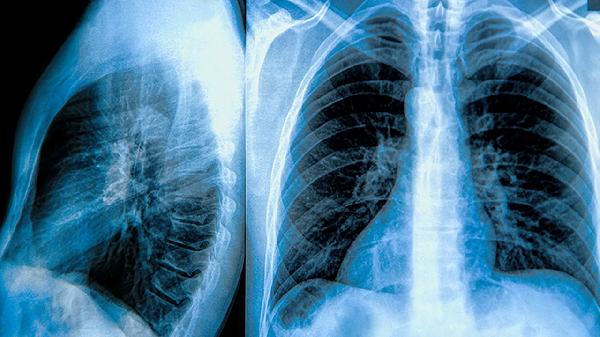

二十五味肺病丸作为藏药复方制剂,其成分中不含明确肝毒性药材,在常规剂量下经肝脏代谢时较少引发异常。临床观察显示,多数患者在医生指导下按疗程服用后,肝功能指标通常保持稳定。该药通过多靶点作用缓解咳嗽、痰多等呼吸系统症状,其代谢产物主要经肾脏排泄,对肝脏的直接刺激较小。